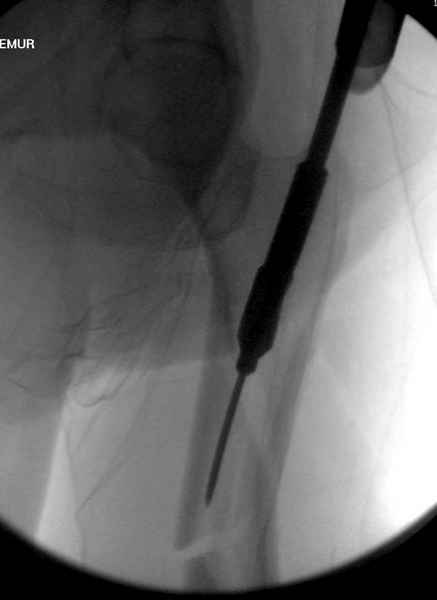

Учитывая, что случай ургентный, больной поступил вечером, не стали делать вытяжение и срочно провели операцию по фиксации перелома бедра антеградным штифтом Versa Nail от DePuy.

Для профилактики дальнейшего раскола в шейке предварительно во время проксимального рассверливания спереди и сзади провели временные спицы, которые в дальнейшем были заменены на шурупы (miss nail method)